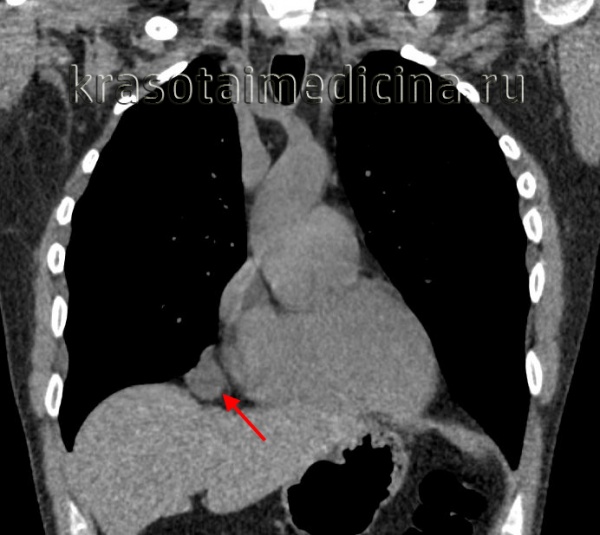

Обязательный перечень рентгенологических исследований включает рентгенографию грудной клетки, рентгенографию пищевода с контрастированием, компьютерную томографию. В большинстве случаев проведенное обследование позволяет установить локализацию рака средостения и распространенность процесса, заинтересованность органов грудной полости (легких, диафрагмы, аорты, грудной стенки). Уточнить состояние мягких тканей в зоне новообразования, выявить метастазы опухоли в лимфоузлы и легкие помогает МРТ.

- Томографическая диагностика. Для более детальной оценки структуры, толщины стенок кисты, характера содержимого и взаимоотношения с соседними анатомическими образованиями, производится КТ и МРТ средостения.